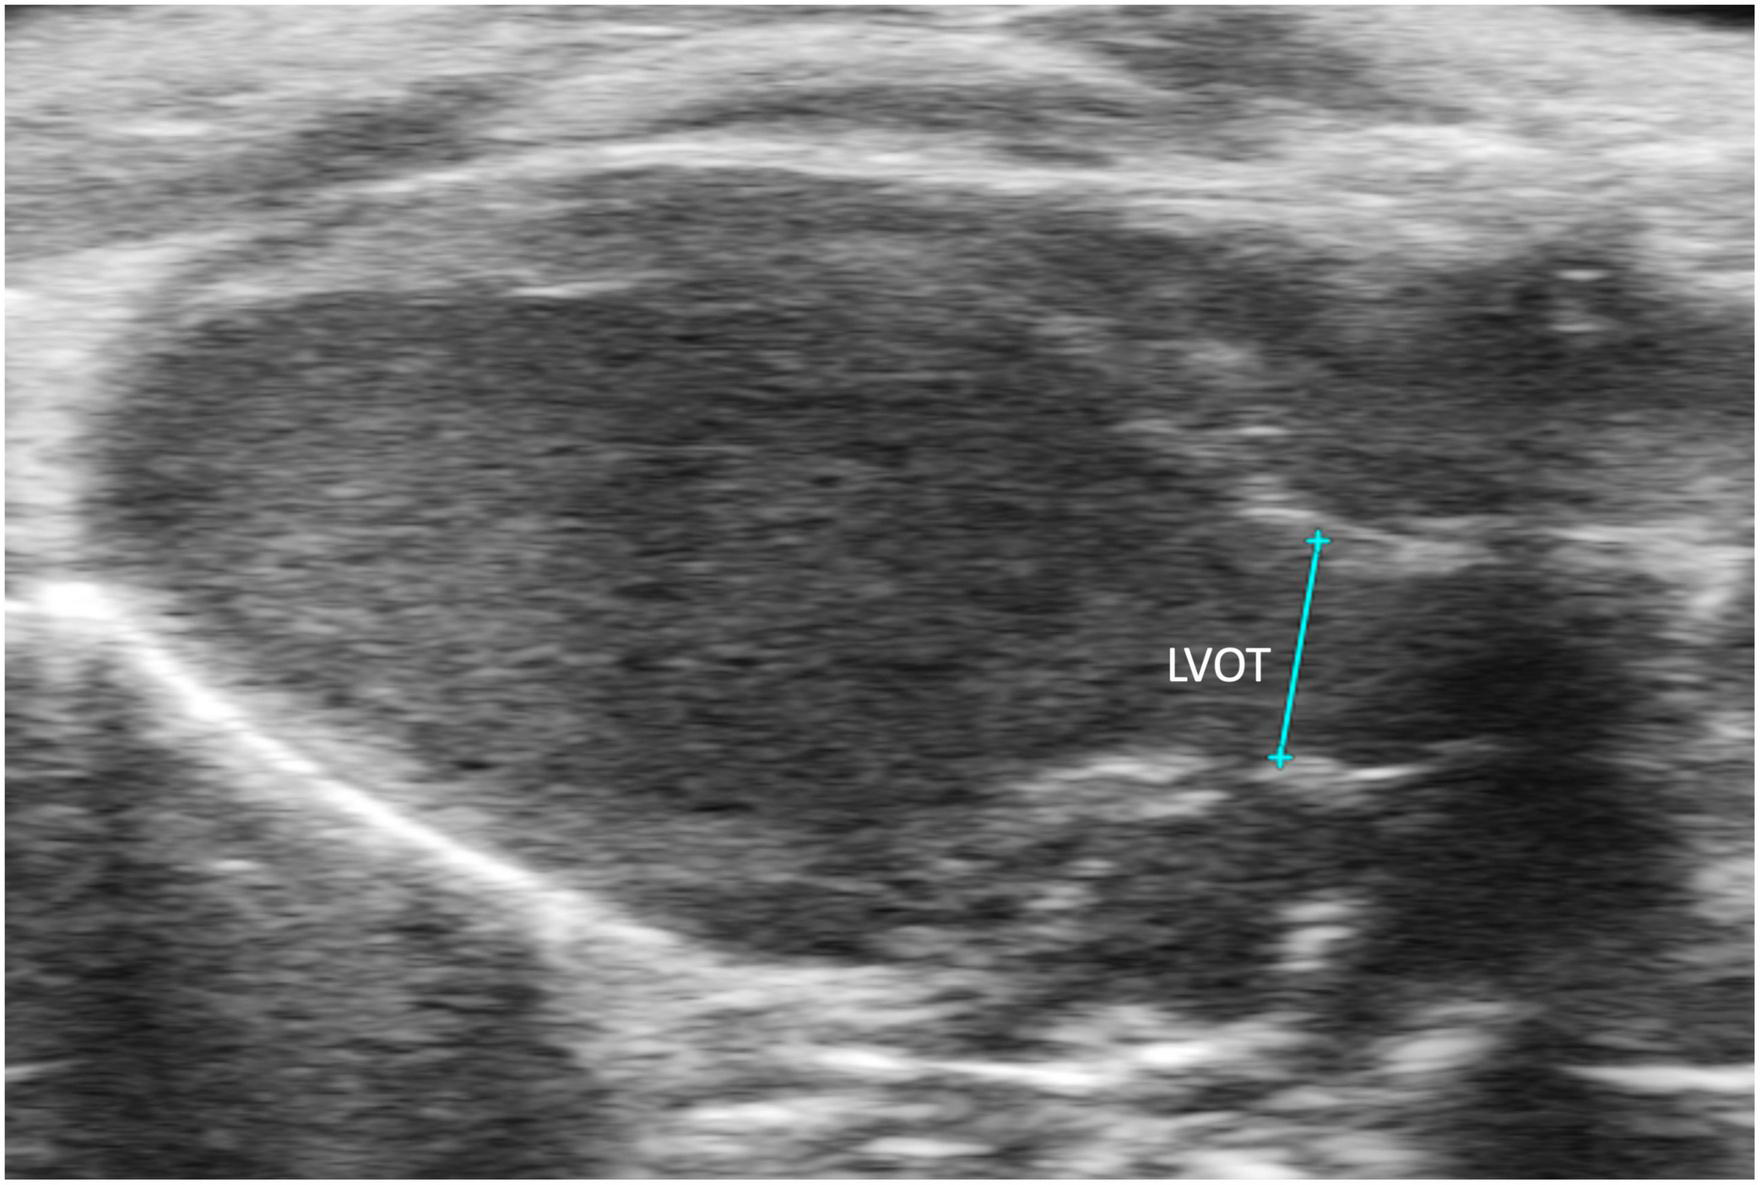

2.3.2.1 Left ventricular outflow length

Left ventricular outflow tract length (LVOT) measures, in millimeters, the left ventricular outflow tract, just proximal to the aortic valve, at end diastole. It is measured by selecting “LVOT” under “AoV Flow” in a PLAX B-mode image containing the left ventricular outflow tract (Figure 9). LVOT would be a valuable measure for mouse models of aortic stenosis because it can be used to calculate aortic valve area (AVA) (see below).

FIGURE 9

The left ventricular outflow tract (LVOT) length is acquired in the B-mode of the parasternal long axis view (PLAX).